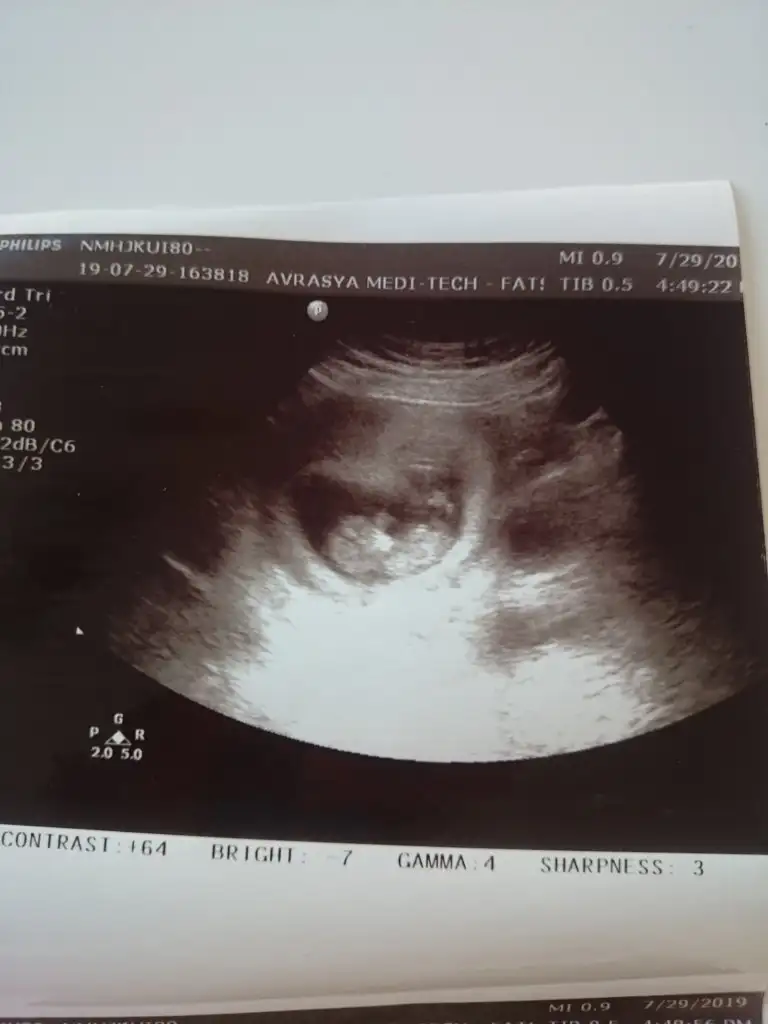

dr soylemeden siz gorun genital nub teorisi ( bebegin cinsiyeti)

14+4 ablamın bebeği. Rica etsem tahminde bulunur musunuz? :KK54:

Bu arada genelde tahminleriniz doğru çıkıyor . inş bunda yanlış çıkar😔 3 kız var bu 4. Çocuk oluyor gönlümüzden hayırlısıyla erkek geçiyor. Sağlıklı doğsun da inş.:emir_bebek:

Bana erkek gibi geldi cnm skull teorisine gore oyle benzetim. o arada hep dogru cikmiyor tahminler bana burda herkes erkek dedi bense skull a gore kiza benzetiyordum simdi ikinci kizim yolda gercekten. Tabi herseyden onemlisi saglikla dogmalari rabbim saglikli hayirli evlat nasip etsin gonlunuze gore versin.